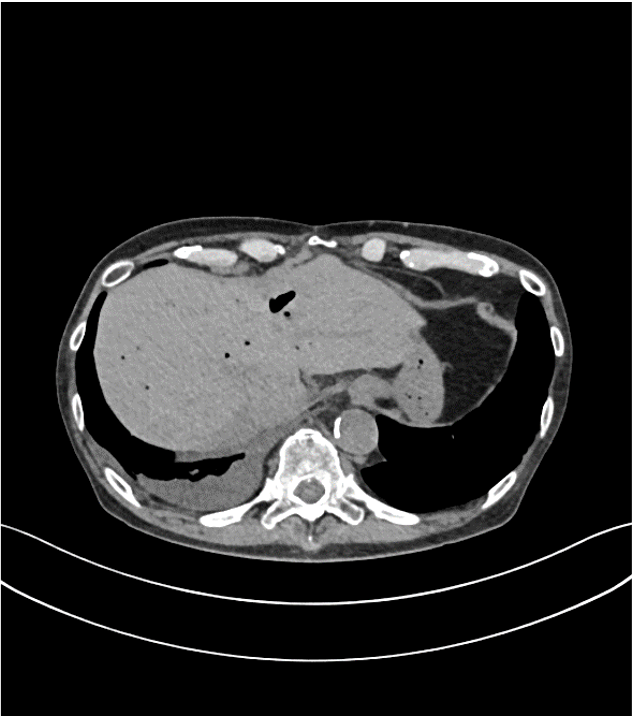

70歳代、男性、60kg、転移性下大静脈内腫瘍、転移性肝腫瘍、転移性肺腫瘍

十二指腸乳頭部癌術後。転移性肝、肺腫瘍術後。ヨード造影剤アレルギー歴あり。肺生検前の心臓超音波検査で下大静脈内腫瘍が疑われ、腫瘍進展範囲確認のため造影MRI検査を施行。

症例解説

十二指腸乳頭部癌術後。転移性肺、肝腫瘍のため左肺下葉、肝S6亜区域切除術後(いずれも30年ほど前)。ヨード造影剤アレルギー歴あり、近年造影CTは行っていない。新たな肺結節が出現し、肺部分切除による生検予定となったが、心臓超音波検査で下大静脈内腫瘍が指摘された。